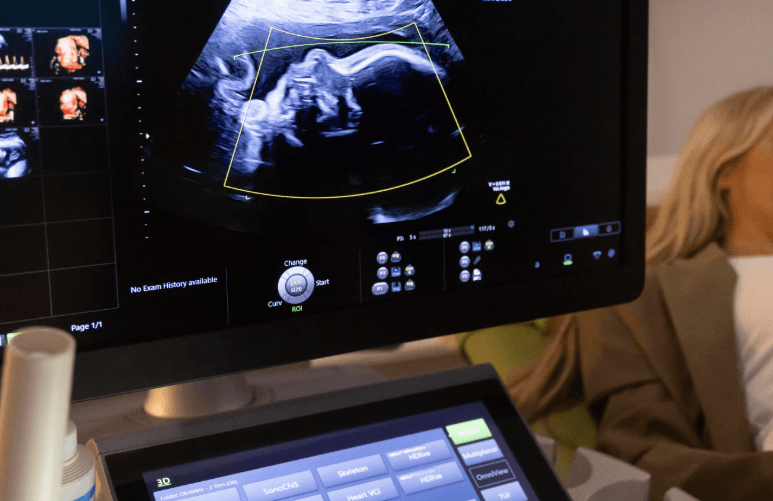

Hamilelik süreci boyunca birçok kez ultrason muayenesine girersiniz ancak "Detaylı Ultrason" (veya halk arasındaki adıyla 2. düzey ultrason), diğerlerinden çok farklıdır. Bu muayene, bebeğinizin sadece boyuna veya kilosuna bakmakla kalmaz; tepeden tırnağa tüm organ gelişimini, plasentanın konumunu ve olası yapısal anomalileri inceleyen bir "check-up" niteliğindedir. Bu tarama süreci, gebeliğinizin en önemli duraklarından biri olduğu için sonuçları mutlaka doktorunuza danışarak değerlendirmelisiniz.

Bu muayene genellikle bir perinatolog (Maternal-Fetal Tıp uzmanı) tarafından yapılır. Uzman, yaklaşık 30 ile 45 dakika süren bu işlemde şu noktaları titizlikle inceler: